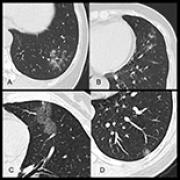

14 Nov 2021 : Clinical Research

Clinical Features and Temporal Lung Radiographic Changes in 25 Patients Recovering from COVID-19 Pneumonia: A Retrospective Case-Control Study

Chao Hu, Jian Ping Zeng, Ke Peng, Hong Xia, Huan Ming Zhang, Zhi Zhong, Ming Yan Jiang

DOI: 10.12659/MSM.933381

Med Sci Monit 2021; 27:e933381

3,640 973 0

3640 973 0